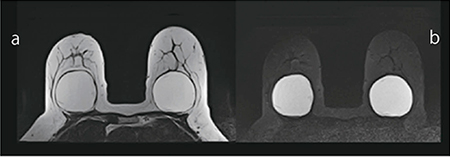

図1 シリコンインプラント画像

a:PASTA-Si。脂肪とシリコンは高信号に,

水および生理食塩水は低信号に描出されます。

b:脂肪抑制PASTA-Si。シリコンのみが高信号に,

水および生理食塩水,脂肪は低信号に描出されます。